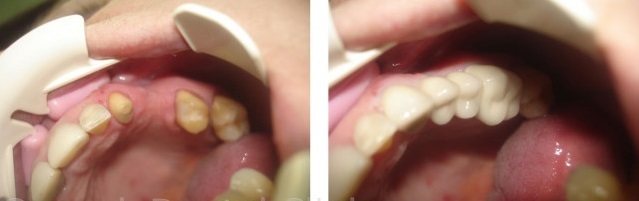

Гемисекция: фото до и после